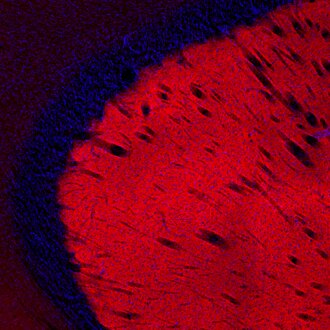

Receptor Proteins

Receptors are proteins or protein complexes located in the membrane of cells that receive chemical signals and trigger a defined cellular response. Receptor proteins include metabotropic, ionotropic and enzyme linked hormone receptors.